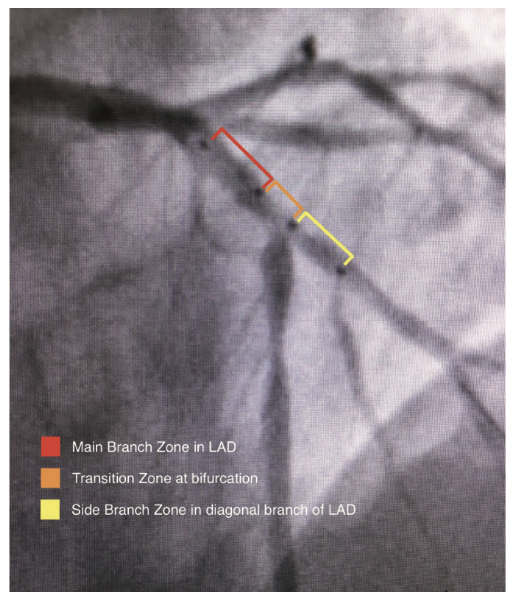

The Tryton side branch stent (Cordis, A Cardinal Health company) is the first FDA-approved stent designed specifically for bifurcation lesions. The specialized design of the Tryton stent has three distinct zones demarcated with radiopaque markers for proper placement at the side branch, which allows for minimal metal-to-artery ratio in the proximal segment and ease of integration of the traditional drug-eluting stent (DES) in the main vessel (Figure 2).2 In this report, we describe a novel utilization of the CorPath GRX robotic heart catheterization system for precise placement of a Tryton side branch stent.

A coronary angiogram was performed, revealing a critical bifurcation stenosis of the mid left anterior descending artery (LAD) and a large diagonal branch vessel which was felt to be the culprit vessel causing her symptoms (Figure 3). Using the CorPath from a 6 French radial approach, a guidewire was placed across the lesion into the diagonal branch of the LAD and a second guidewire was placed across the lesion into the mid LAD (Figure 4). After pre-dilating the lesion, the CorPath was used to measure the longitudinal length of the diagonal branch at the ostium. An appropriately sized Tryton stent was placed over the diagonal branch guidewire and advanced to the site of the lesion. The stent was then carefully advanced by utilizing the CorPath such that the mid-markers precisely straddled the ostium of the diagonal branch to within 1 mm (Figure 5). The Tryton stent delivery system balloon was inflated and the stent was successfully deployed in an appropriate position (Figure 6). The Tryton stent balloon was withdrawn and the diagonal branch guidewire was rewired through the transition zone of the Tryton stent into the main vessel distal to the ostium of the diagonal branch, taking care not to retract proximal to the Tryton stent. Once the guidewire was successfully placed in the LAD through the transition zone, the “trapped” original LAD guidewire was removed (Figure 7). The length needed for the LAD stent was measured from the proximal edge of the Tryton stent to beyond the distal edge of the LAD lesion, and a drug-eluting stent (DES) was advanced over the same guidewire into position within the main branch zone of the Tryton stent and extending into the LAD, and then deployed. After removal of the DES balloon, an additional guidewire was selected and advanced into the diagonal branch, taking care to ensure that it was advanced within the lumen of the LAD stent. Two appropriately sized balloons were selected and advanced into position in the diagonal branch and LAD along their respective guidewires. Simultaneous kissing balloon inflation was performed (Figure 8). Repeat angiography confirmed adequate stent expansion and demonstrated dramatic improvement in coronary perfusion (Figure 9).

The treatment of bifurcation lesions with percutaneous intervention continues to present a unique challenge to interventional cardiologists. Due to the geometric limitations of traditional drug-eluting stents, the procedure often requires additional time and can be technically difficult. Treatment of bifurcations has been traditionally performed with various techniques, using traditional stents, but each strategy has its own advantages and limitations, and no technique is suitable for every lesion. Several creative methods have been employed, including provisional stenting, V-stenting, simultaneous kissing stent double barrel technique, the crush technique, T-stenting, and the culotte technique, each with its specific advantages and limitations. The common practice of provisional stenting is often susceptible to complications such as restenosis of the side branch. Other stenting techniques using traditional stents can create problems with complete lesion coverage and increased metal-to-artery ratio in the proximal segment.3 As interventionalists search for more definitive treatment of these common lesions, there have also been reports of modifications of the above techniques from various approaches, such as a recently described modified crush technique from a radial approach.4 The Tryton side branch stent, which was also placed using a radial approach in this case, incorporates a Tri-Zone technology design with a specially sized side branch zone, a transition zone for full coverage of the ostium with proper placement, and a main branch zone with minimal metal-to-artery ratio for easier rewiring of the main vessel in order to integrate a DES. These zones are demarcated with radiopaque markers to aid in precise placement at the side branch prior to rewiring the main branch. Accurate placement of the Tryton stent is paramount for full vessel coverage of the side branch with the side branch zone, while keeping the ostium of the main branch open for efficient rewiring and placement of traditional DES.5